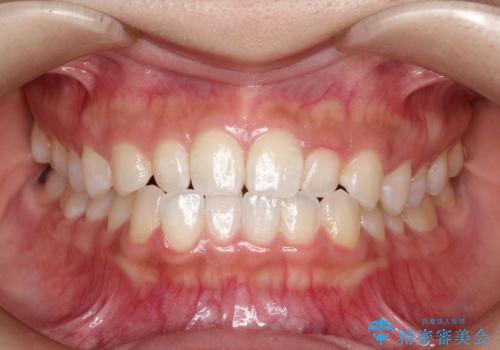

- 前歯の凸凹を主訴に来院された患者様です。

カウンセリング時に、側切歯が矮小歯であることを指摘したところ、適切な幅径での修復を希望されました。

インビザラインを用い、計画通りに歯並びを改善することができました。